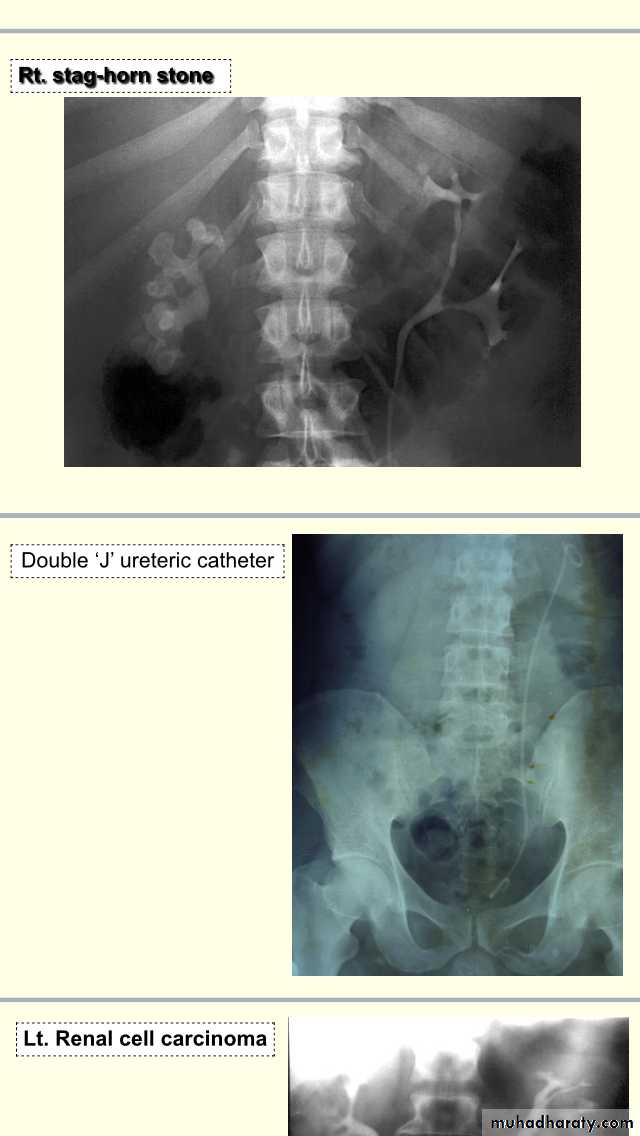

Uroradiology & Slides 1